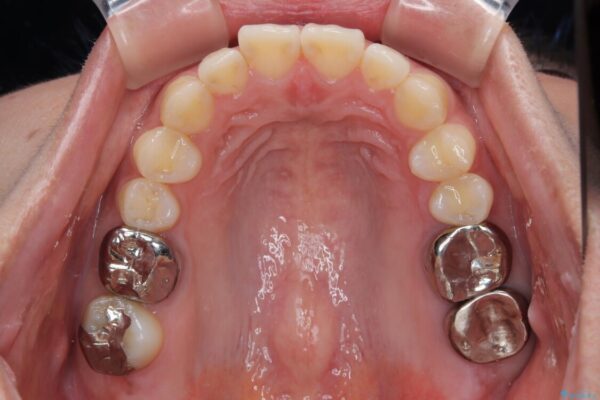

しかし、噛み合わせの相手である右上の第二大臼歯が、長期間噛み合う歯がなかった影響で**挺出(歯が下に伸びてくる状態)してしまっており、このままではインプラントを埋入して被せもの(上部構造)を入れるためのスペースが不足している状態でした。

その後、挺出していた右上第一大臼歯と第二大臼歯に装着されていた銀歯についても、審美性と適合性の向上を目的に、オールセラミッククラウンにやり替えました。

• 挺出歯を圧下してスペースを確保!目立たない部分矯正で下顎大臼歯にインプラント治療を実現 治療前画像